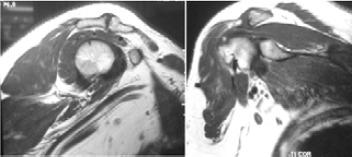

Shoulder impingement syndrome and acromioclavicular joint osteoarthritis often occur simultaneously and easily missed. Kay et al. reported excellent results with combined arthroscopic subacromial decompression and resection of the distal end of the clavicle in patients with both disorders(1). Arthroscopic treatment of these disorders produces more favourable results than open procedures. We report two patients who were not responding to conservative management and were treated with direct arthroscopic distal clavicle excision and subacromial decompression in single setting. Both patients gained good postoperative outcome in terms of pain score, function and strength improvement assessed objectively with visual analogue score (VAS) and University of California Los Angeles Score (UCLA).